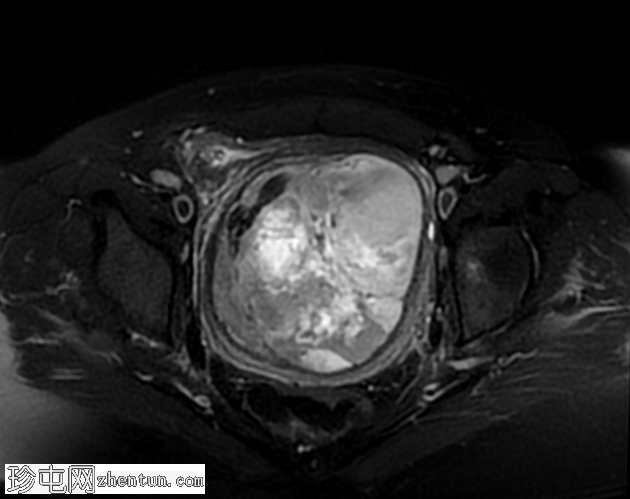

轴位T2

脂肪饱和度

在T2加权图像上,病变呈中高信号,伴有囊性变性区域,以及与T1暗区相对应的偏心T2暗信号,也与含铁血黄素相符。

T2加权成像中的低信号区域可能是由于流空或病灶内含铁血黄素所致。该影像学特征在平滑肌肉瘤 (LMS) 诊断中表现出良好的诊断价值,敏感性为79%至84%,特异性约为86%。将这些表现与良性平滑肌瘤中常见的低T2信号区分开来至关重要。 T1加权图像与增强模式的相关性有助于准确鉴别。